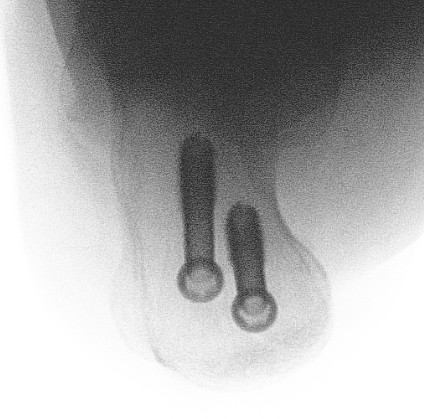

Xrays

Screw fixation

Poor bone quality

- 2 - 3 screws

- bicortical fixation

- fully threaded screws for extra fixation

- consider washers

- dont but screw heads too close to each other or fracture (risk of comminution)

Fixation failure with screws